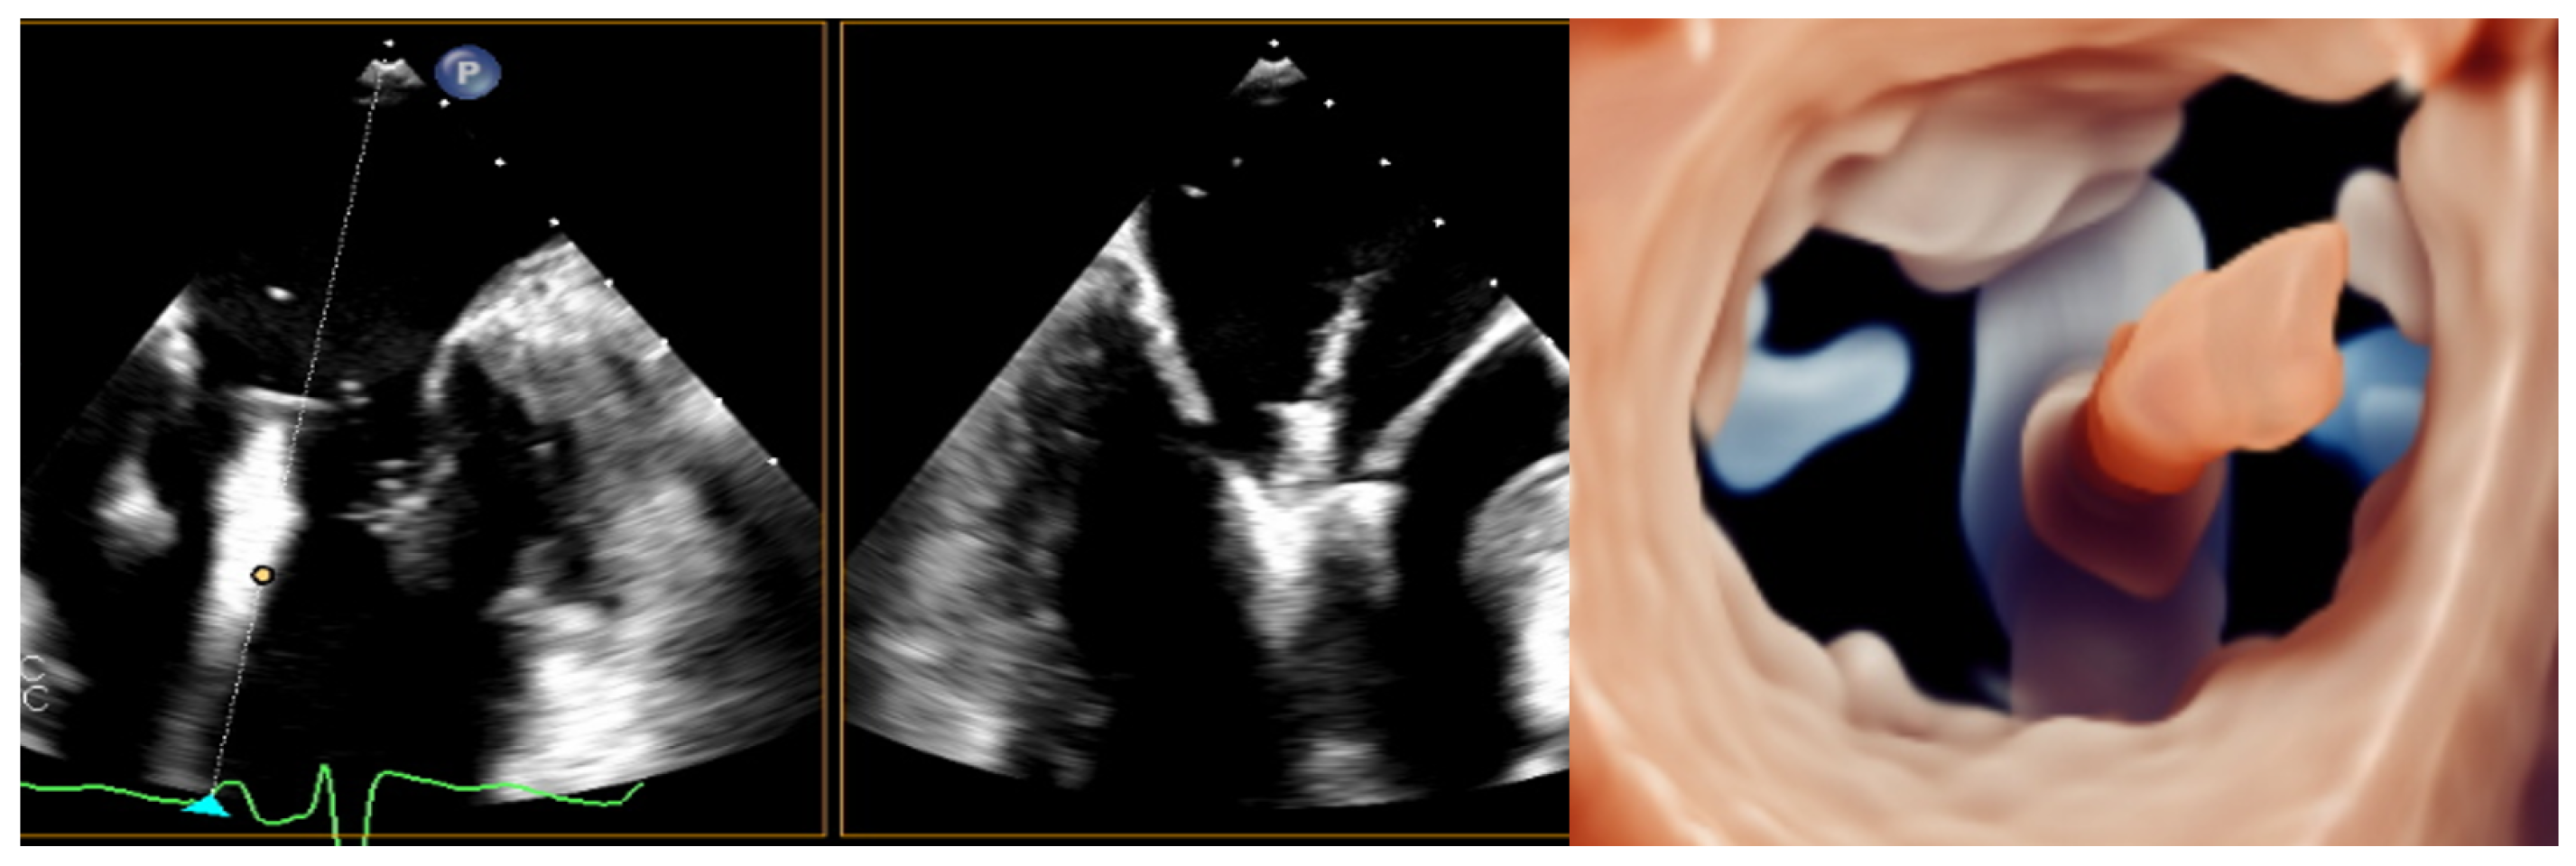

5.a Transcatether Edge-to-Edge Repair

5.e TMVR